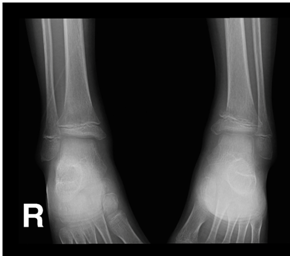

A 9-year-old Saudi boy presented to the emergency department complaining of pain in his ankles, with a history of trauma and difficulty walking. He had this trauma one month before reporting to the hospital and was described as trivial by parents. The patient had no history of fever and no change in his weight. On examination, he was afebrile. Neurological exam was normal but he was unable to walk. The X-ray radiograph showed that the posteromedial part of the distal metaphysis of the left tibia had an abnormal configuration with an irregular margin. Furthermore, as shown in Figures 1 & 2, there was a decrease in tibio-talar joint space bilaterally and a general decrease in bone density. Investigations showed the following values: platelet count: 91; an absolute neutrophil count: 0.2; hemoglobin: 9; and WBC: 2000. Vitamin D, calcium, and bone marrow aspiration tests revealed a marked decrease in the vitamin D level and a 97% blast in the bone marrow, as shown in Figure 3. Flow cytometry showed positivity for CD19, CD22, CD33, CD34, CD10, CD79a, TdT, CD11b, and HLA-DR. The patient was put on chemotherapy, Tazocin, cotnmoxazol, nystatin, and sodium bicarbonate. Thereafter, his lower limb pain significantly improved and he started to walk normally.

Figure 2 Lateral view

Figures 1 & 2 Posteromedial part of the distal metaphysis of the left tibia with abnormal configuration and irregular margin.